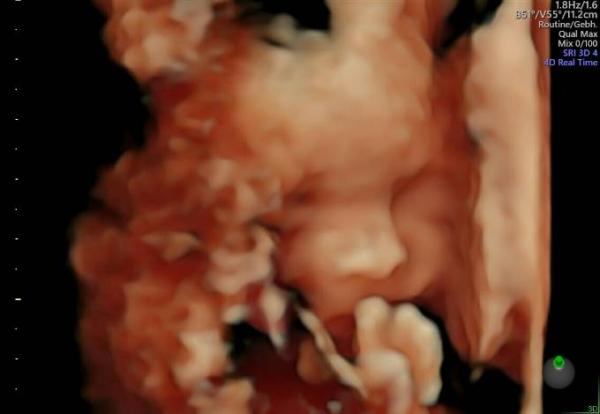

Es war echt lustig, ihr ein bisschen neben der Vermessung zuzuschauen. Auf dem Bild seht ihr, wie sie fast ihren Fuß in die Nase steckt. Sehr akrobatisch. Ansonsten ist ihr Kopf schön eingebettet zwischen Plazenta und meiner Bauchdecke. War wohl deswegen etwas schwer, sie im Gesicht so einzufangen. Der Arzt hat sich sehr über den eingetragenen ET gewundert. Ich meinte, dass resultiert aus der ersten Vermessung in der siebten Woche. Nach meiner Berechnung war es ja der 11.7., im Mutterpass steht 15.7. und er sagt jetzt 10.7. Sogar bei dem Datum ist alles noch überdurchschnittlich. Sie ist recht kräftig. Hat sie ihm auch gleich gezeigt und kräftig mit den Händen geboxt, sodass er es sehen und spüren konnte. Sie wiegt jetzt etwa 510g und ist ca 25 cm groß. Habt ihr die Bilder auch auf CD bekommen? Da sind sogar kleine Videos drauf. Tolle Erinnerung! Meine Kinder waren auch begeistert. In einer Woche habe ich dann Vorsorge bei meiner Hebamme. Darauf freue ich mich schon.